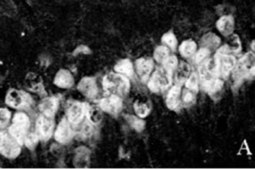

Immunocytochemistry:

1:10-1:100 dilution from a previous lot was used. Neurons in culture should be permeablized with 0.1% triton X-100. All primary antibody dilutions should be performed with simple solutions containing only buffer and primary antibody without excess protein blocks or detergents.

MILLIPORE′s exclusive monoclonal antibody to vertebrate neuron-specific nuclear protein called NeuN (or Neuronal Nuclei) reacts with most neuronal cell types throughout the nervous system of mice including cerebellum, cerebral cortex, hippocampus, thalamus, spinal cord and neurons in the peripheral nervous system including dorsal root ganglia, sympathetic chain ganglia and enteric ganglia. Developmentally, immunoreactivity is first observed shortly after neurons have become postmitotic, no staining has been observed in proliferative zones. The immunohistochemical staining is primarily localized in the nucleus of the neurons with lighter staining in the cytoplasm. The few cell types not reactive with MAB377 include Purkinje, mitral and photoreceptor cells. The antibody is an excellent marker for neurons in primary cultures and in retinoic acid-stimulated P19 cells. It is also useful for identifying neurons in transplants.

Anti-NeuN antibody (NEUronal Nuclei; clone A60) specifically recognizes the DNA-binding, neuron-specific protein NeuN, which is present in most CNS and PNS neuronal cell types of all vertebrates tested. NeuN protein distributions are apparently restricted to neuronal nuclei, perikarya and some proximal neuronal processes in both fetal and adult brain although, some neurons fail to be recognized by NeuN at all ages: INL retinal cells, Cajal-Retzius cells, Purkinje cells, inferior olivary and dentate nucleus neurons, and sympathetic ganglion cells are examples (Mullen et al., 1992; Wolf et al., 1996). Immunohistochemically detectable NeuN protein first appears at developmental timepoints that correspond with the withdrawal of the neuron from the cell cycle and/or with the initiation of terminal differentiation of the neuron (Mullen et al., 1992). Immunoreactivity appears around E9.5 in the mouse neural tube and is extensive throughout the developing nervous system by E12.5. Strong nuclear staining suggests a nuclear regulatory protein function; however, no evidence currently exists as to whether the NeuN protein antigen has a function in the distal cytoplasm or whether it is merely synthesized there before being transported back into the nucleus. No difference between protein isolated from purified nuclei and whole brain extract on immunoblots has been found (Mullen et al., 1992).